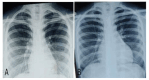

Figure 2

X-ray posteroanterior view before (A) and after (B) starting liposomal amphotericin B therapy